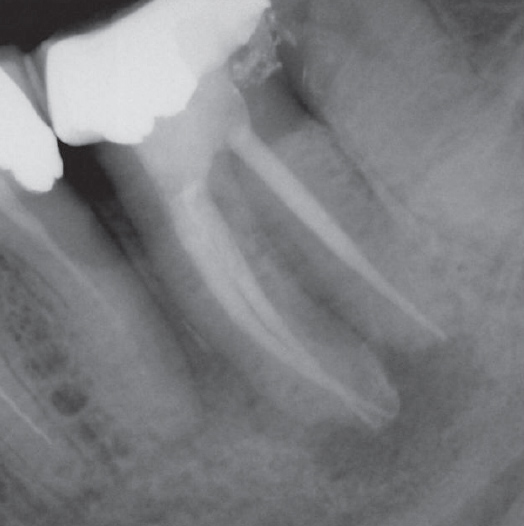

Before

After

Before Root Canal treatment

After Root Canal treatment